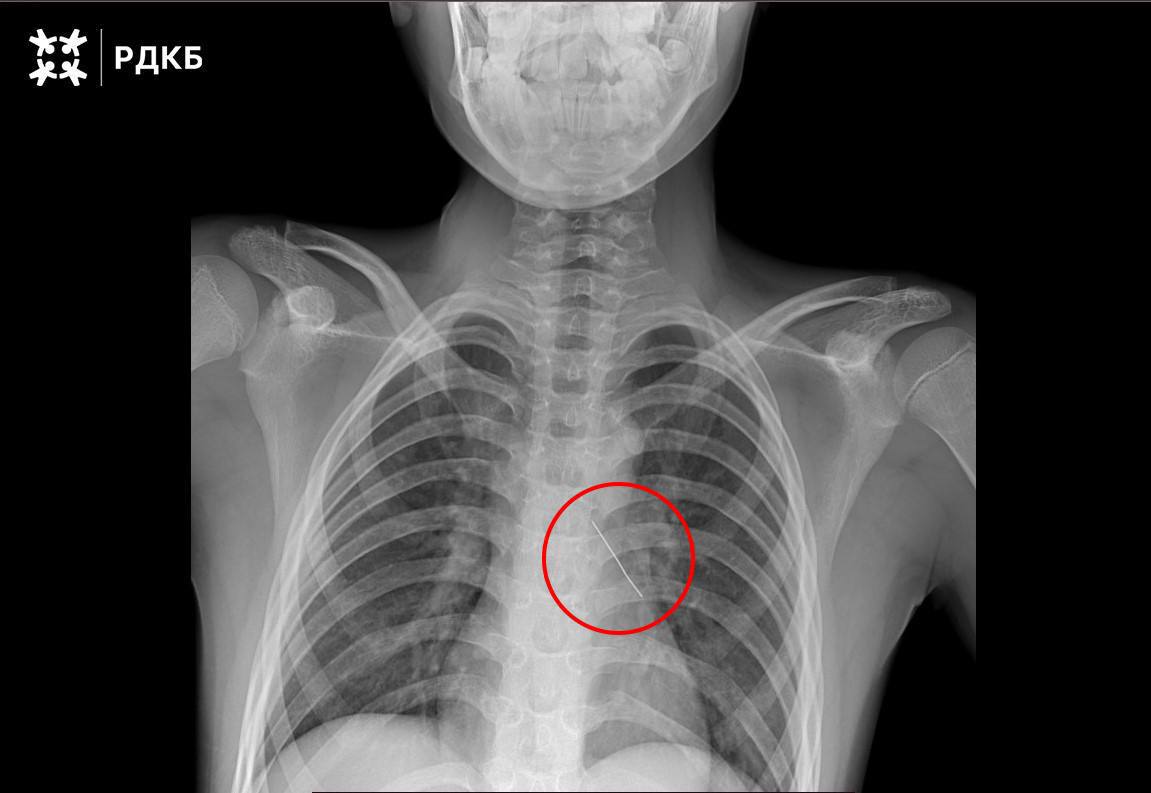

В Москве подросток проглотил острую булавку, которая пронзила бронх. Медики провели экстренную операцию, чтобы предотвратить коллапс лёгкого.

В Москве подросток проглотил острую булавку, которая пронзила бронх. Медики провели экстренную операцию, чтобы предотвратить коллапс лёгкого.

В Москве подросток проглотил острую булавку, что привело к серьёзным осложнениям со здоровьем. Инородный предмет пронзил бронх, вызвав проблемы с дыханием. Пострадавший мог говорить только шёпотом и жаловался на сильную боль в груди.

Медики диагностировали риск коллапса лёгкого и немедленно приступили к операции. Булавка была успешно извлечена, что предотвратило потенциально опасные последствия. Сейчас подросток находится под наблюдением врачей, его состояние стабилизировалось.

Этот случай ещё раз подчеркивает важность осторожности при обращении с мелкими предметами, особенно в быту. Медики напоминают, что при проглатывании инородных тел необходимо незамедлительно обращаться за медицинской помощью.